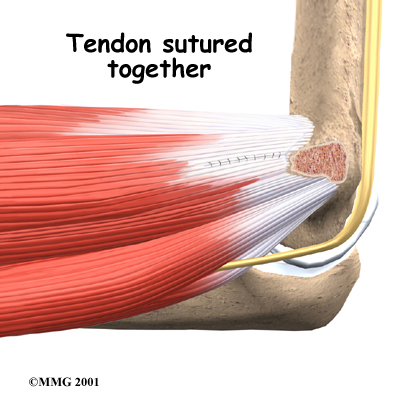

The flexor tendon is then cut where it connects to the medial epicondyle. The surgeon splits the tendon and takes out any extra scar tissue. Any bone spurs found on the medial epicondyle are removed. (Bone spurs are pointed bumps that can grow on the surface of the bones.) Some surgeons suture the loose end of the tendon to the nearby fascia tissue. (Fascia tissue covers the muscles and organs throughout your body.)

The following images show each step:

Tendons Reattached